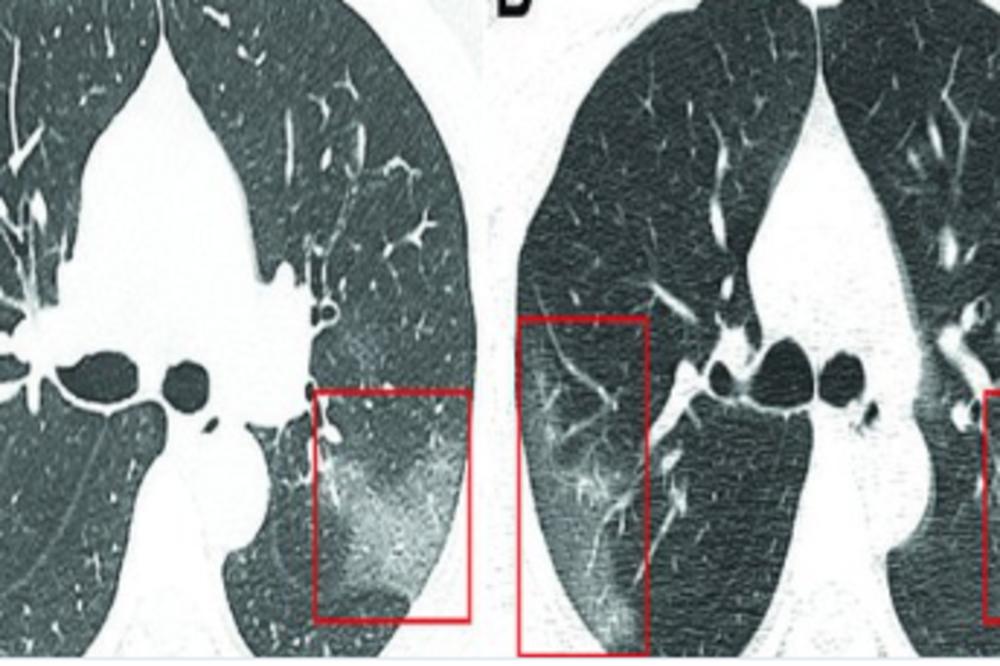

Na snimcima su lekari uočili bele senke, poput takozvanog mlečnog stakla, što ih je upozorilo na to da su pluća delimično ispunjena tečnošću.

Lekari kažu da je u početku vrlo lako pomešati koronavirus sa upalom pluća. Skener je pokazao da se kroz tri dana stanje pacijenta pogoršava, što je bio slučaj i sa SARS-om i MERS-om, virusima koji su takođe harali Kinom početkom 21. veka. Na narednom skeneru su lekari uočili da su bele fleke izraženije što je isključilo upalu pluća i pomoglo im da shvate da treba na drugačiji način da se bore sa ovom bolešću jer obični antibiotici neće pomoći.